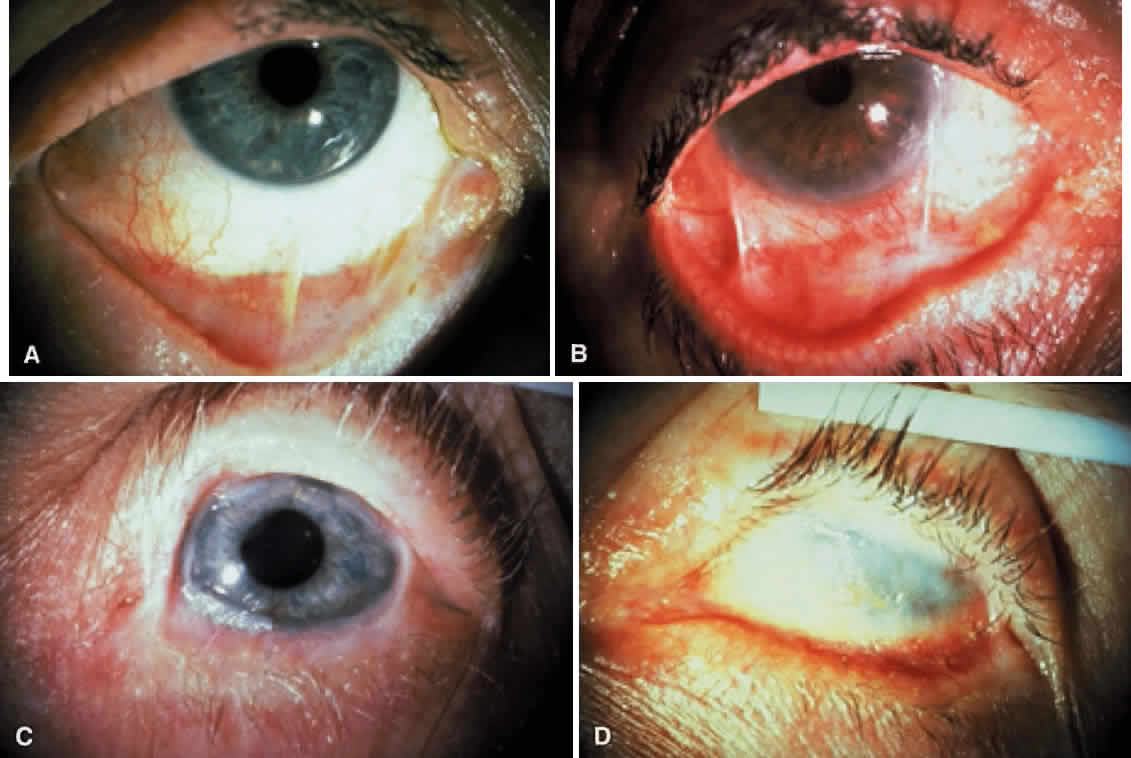

Fibrosis beneath the conjunctival epithelium is the hallmark of CP.9,10 Symblepharons, fibrotic bands that pass between the palpebral and bulbar conjunctiva, involve the inferior fornix first and are best demonstrated early in the disease by drawing the lower eyelid down and having the patient look up (Fig. 3). CP may be associated with a dry eye. Fibrosis beneath the conjunctival epithelium may cause occlusion of the ducts of the lacrimal and accessory lacrimal glands, leading to decreased aqueous tear secretion. The reduced numbers of mucus-producing goblet cells may contribute to an unstable tear film.11 Conjunctival scarring causes lagophthalmos with abnormal blinking and exposure and entropion with trichiasis and distichiasis. All these factors may cause breakdown of the ocular-surface epithelium.

Cicatricial pemphigoid generally runs a chronic course, characterized by progressive shrinkage of the conjunctiva. When the end stage of this disease is reached, the eye lacks tears and has obliterated conjunctival fornices, ankyloblepharon, and a keratinized ocular surface epithelium. Episodes of acute disease activity may interrupt this chronic progressive course and result in rapid shrinkage of the conjunctiva.15 Acute disease activity may be precipitated by surgical procedures, including conjunctival biopsy, lysis of symblepharon, oculoplastic procedures on the eyelids, and cataract extraction. The acute manifestations consist of localized, ulcerated conjunctival mounds (Fig. 4) or diffuse, severe conjunctival hyperemia and edema (Fig. 5). Before concluding that acute inflammatory activity is caused by the disease process, it is necessary to eliminate other confounding factors such as trichiasis, exposure, or bacterial blepharoconjunctivitis.